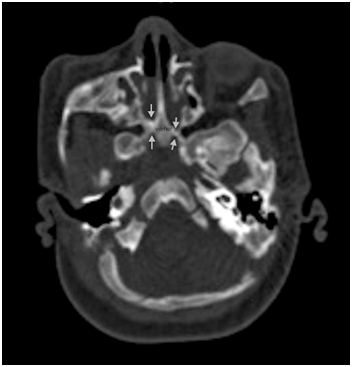

Choanal atresia (CA) is a congenital anomaly arising from failure of canalization of the posterior nasal passage (the choana) which forms the communication between the nose and pharynx.1 Normally, canalization occurs during embryological development between the 4th and 11th weeks of gestation.2 Failure of canalization results in a persistent bucco-pharyngeal membrane or naso-buccal blockage,3 either bony or membranous in structure. CA can occur unilaterally or bilaterally.1,4 Estimated prevalence of CA ranges between 1 per 7000 to 8000 live births. Two-thirds of the cases are unilateral while one third are bilateral. It is twice as common in females.5 Twin pregnancies; chromosomal anomalies and antithyroid treatment during gestation are possible risk factors for CA.6 Since neonates are obligate nasal breathers, bilateral cases are detected at birth due to severe respiratory difficulties and are considered neonatal emergencies. The diagnosis is initiated when a soft catheter cannot pass transnasally, and confirmation is done by a CT scan (Figure 1).1

Figure 1 CT scan of nose and paranasal sinuses showing bilateral choanal atresia (arrowns). Note also thickening of vomer.